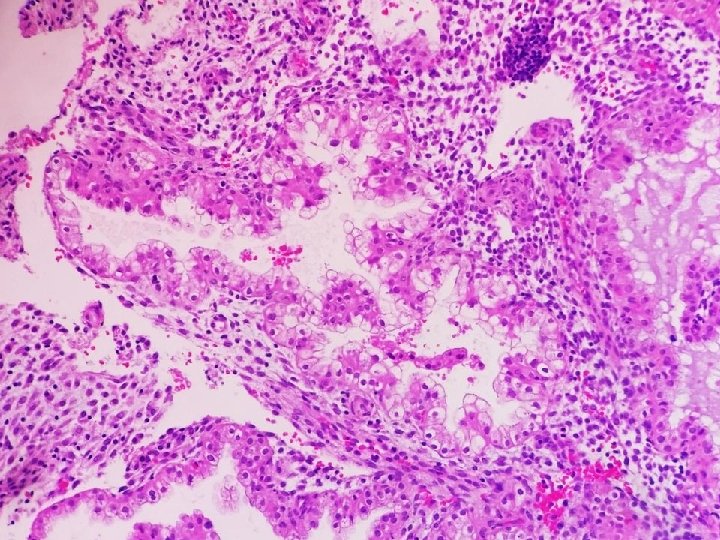

Diagnóstico Anatomopatológico • 1. - Trompa Uterina Derecha (Salpinguectomía) – Malformación Arteriovenosa • 2.

Diagnóstico Anatomopatológico • 1. - Trompa Uterina Derecha (Salpinguectomía) – Malformación Arteriovenosa • 2. - Útero (legrado) – Restos deciduocoriales compatibles con embarazo intrauterino.

Malformación arteriovenosa en el tracto genital femenino • • Rara entidad. > Útero <

Malformación arteriovenosa en el tracto genital femenino • • Rara entidad. > Útero < anejos (conjunto 100 casos) Congénito / adquirido Asociación EE – MAV